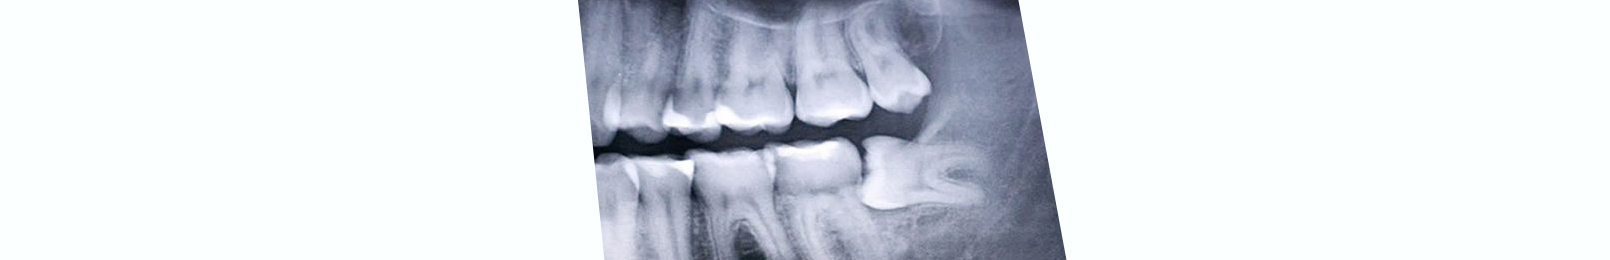

Dirt on teeth (tartar, plaque and stains) is a common cause of serious dental problems such as;

• Bad breath(halitosis).

• Tooth decay(cavities).

• Gum disease.

• Dental infections.

• Discolored teeth, etc.